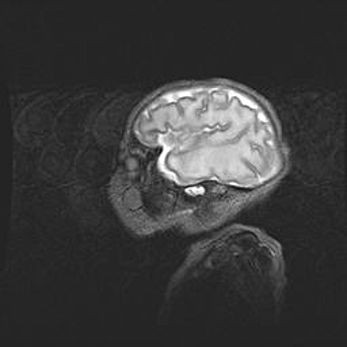

Церебральная ишемия II.

Возраст: 5 дней

Вес: 3400 г

Пол: женский

Окружность головы: 35 см

Срок гестации: 39 недель

Церебральная ишемия – это заболевание, характеризующееся недостаточностью (гипоксией) либо полным прекращением (аноксией) снабжения мозга кислородом по причине закупорки одного или нескольких сосудов. Это приводит к  что метаболическим расстройствам различной степени тяжести в тканях головного мозга, развитию коагуляционных некрозов и гибели нейронов.